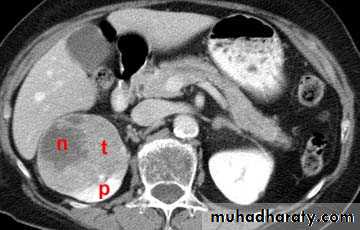

CT scanContrast enhanced CT scan through the kidneys in nephrogram phase 90-100 seconds following contrast administration and would show renal lesions well.

Contrast enhanced CT scan through the kidneys in pyelogram phase (showing excretion of contrast into the collecting system). This is approximately 10-15 minutes following contrast administration and would show urothelial lesions well, such as transitional cell carcinoma, stones, blood clots.